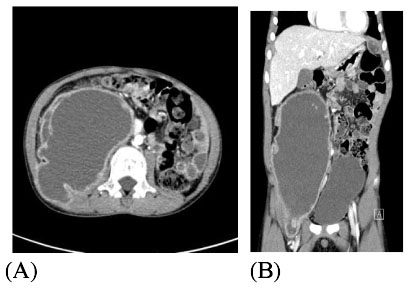

(A). A cross sectional view of the abdominal CT with contrast shows 16 × 4.6 cm sized iliopsoas abscess with enhancing rim on the right side of the abdomen. (B). In an axial view, increased sized multiple intraabdominal abscesses were seen under the subcapsular area of the liver and left subphrenic area.

Fig. 2 (A). A cross sectional view of the abdominal CT with contrast shows 16 × 4.6 cm sized iliopsoas abscess with enhancing rim on the right side of the abdomen. (B). In an axial view, increased sized multiple intraabdominal abscesses were seen under the subcapsular area of the liver and left subphrenic area.